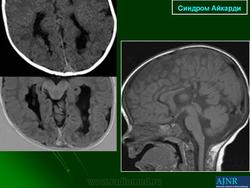

На МРТ можно обнаружить агенезию мозолистого тела, асимметрию полушарий коры, гетеротопию коркового вещества, внутримозговые кисты, папиллому сосудистых сплетений и тд.. Аксоны коры, которые в норме должны перекрещиваться, при его агенезии не формируются и соответственно не идентифицируются при нейровизуализации.

Агенезия мозолистого тела позволяет боковым желудочкам распространиться вверх, во фронтальное и париетальное белое вещество. Это состояние именуется верхней транслокацией боковых желудочков в лобно-теменные регионы мозга. Аналогичное смещение вверх претерпевает и III желудочек , что является одним из нейрорадиологических маркеров агенезии мозолистого тела. Увеличенный III желудочек, выдвигаясь вперед и вверх, раздвигает передние рога боковых желудочков, при сопутствующей гидроцефалии объем желудочков увеличивается, задние рога расширяются и изгибаются по направлению к средней линии (форма «ухвата»). Вероятно отсутствие поддерживающей функции мозолистого тела является основой для типичной черты агенезии мозолистого тела - расширения полушарий, III желудочка и Монроева отверстия.